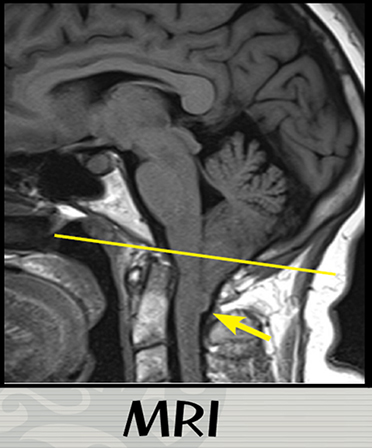

아놀드-키아리 기형은 선천적으로 뇌 조직 (후두부, 소뇌)이 두개골 내의 정상적인 위치에서 벗어나 상부 척추강으로 하방, 확장된 상태입니다. 두개골의 일부가 기형이거나 일반적인 것보다 작아서 뇌를 누르고 아래쪽으로 뇌에 압력이 가해질 때 발생합니다. 아놀드-키아리 기형은 흔하지 않지만 그 정도가 심한 경우 생명 유지나 상,하지의 운동 마비나 보행에 심각한 장애를 일으킬 수 있는 심각한 질환으로 최근 영상 검사의 비약적 발전과 사용이 증가함에 따라 진단이 증가되고 있습니다. ( 그림 1,2 )

노란실선 : 두개골의 기저부를 연결한 선. 정상적으로 소뇌는 이 선의 상부 ( 두개골 내)에 위치해야 함.

노란 화살표 : 노란 실선의 하방은 척추강 내이며 비정상적인 기형으로 인해 소뇌의 일부가 하방으로 내려와 있음.

상태를 진단하기 위해 의사는 병력과 증상을 검토하고 신체 검사를 실시합니다. 자기공명영상(MRI)는 키아리 기형을 진단하는 데 사용되는 가장 중요한 검사입니다. 안전하고 고통 없는 MRI는 증상을 일으키는 뇌의 구조적 차이에 대한 상세한 3D 이미지를 만들어 소뇌의 이미지를 제공하고 그것이 척수로 확장되는지 여부를 알 수 있습니다. MRI는 또한 질병의 진행을 모니터링 하는데 사용됩니다.